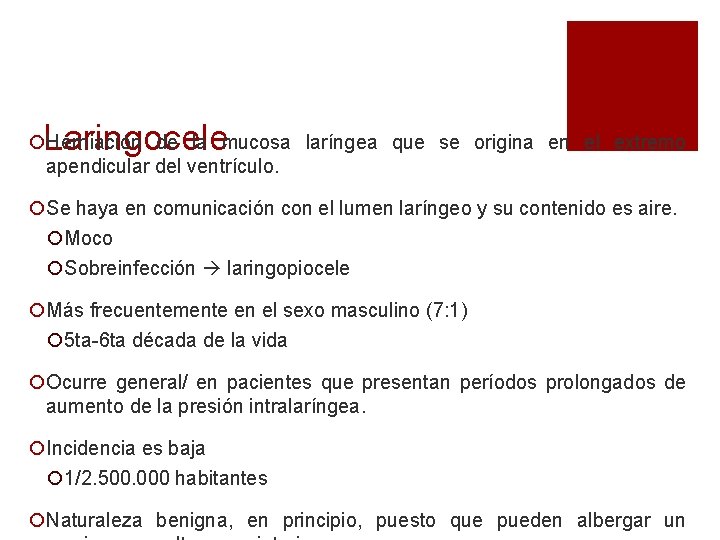

Laringocele ¡Herniación de la mucosa laríngea que se origina en el extremo apendicular del ventrículo. ¡Se haya en comunicación con el lumen laríngeo y su contenido es aire. ¡Moco ¡Sobreinfección laringopiocele ¡Más frecuentemente en el sexo masculino (7: 1) ¡ 5 ta-6 ta década de la vida ¡Ocurre general/ en pacientes que presentan períodos prolongados de aumento de la presión intralaríngea. ¡Incidencia es baja ¡ 1/2. 500. 000 habitantes ¡Naturaleza benigna, en principio, puesto que pueden albergar un

Fisiopatología ¡La fisiopatología del laringocele no es clara, algunas causas serían: ¡sáculo alargado ¡Obstrucción del orificio sacular ¡Aumento de la presión transglótica. ¡ sopladores de vidrio, levantadores de pesas, tosedores crónicos, posparto e interpretes de instrumentos de viento.